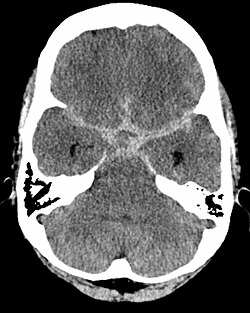

Bild : Subarachnoidale Blutung in den basalen Zisternen (sternförmige Aufhellung in der Mitte)